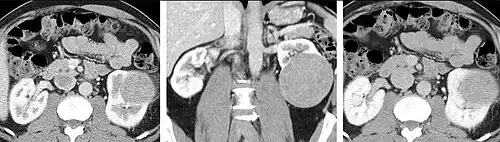

Detection and characterization of renal parenchymal masses is a frequent indication for CT. An initial noncontrast CT is important for detecting calcium or fat in a lesion, and to provide baseline attenuation of any renal masses. Following noncontrast scanning, intravenous contrast is injected and a corticomedullary phase is obtained at approximately 70 seconds (figure 7a, 7b). The corticomedullary phase is characterized by enhancement of the renal cortex as well as the renal vasculature. This phase is valuable in the evaluation of benign renal variants, lymphadenopathy and vasculature, however certain medullary renal masses may not be visible during this phase due to minimal enhancement of the medulla and collecting system. The parenchymal phase is obtained approximately 100–200 seconds after the injection of contrast material (figure 7c). Parenchymal phase imaging demonstrates continued enhancement of the cortex, enhancement of the medulla, and various levels of contrast material in the collecting system. The parenchymal phase is highly important for the detection and characterization of renal masses, parenchymal abnormalities, and the renal collecting system. This method of imaging does not evaluate for abnormalities of the collecting system.

Common renal masses can occasionally be differentiated from each other using this imaging technique. Renal cell carcinomas and oncocytomas typically demonstrate intense heterogeneous enhancement on the parenchymal phase images and cannot be reliably differentiated from each other but can be distinguished from other renal masses. Angiomyolipomas (AML's) also demonstrate intense contrast enhancement but characteristically contain macroscopic fat which can be detected on the noncontrast images, and can help to differentiate AML's from renal cell carcinomas and oncocytomas. Renal lymphoma on the other hand, will often have decreased enhancement when compared to the renal parenchyma on the parenchymal phase images.